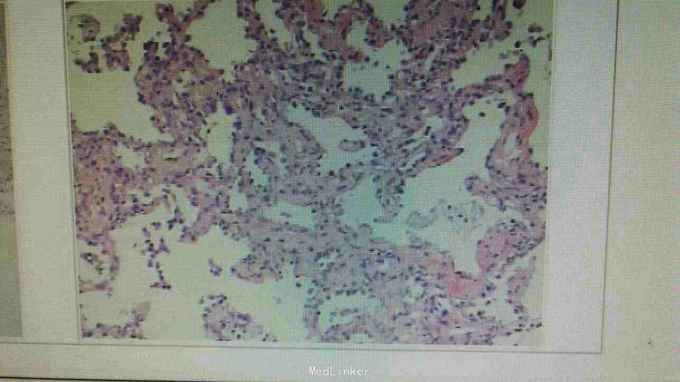

入院诊断肺多发病灶查因:肺梗死伴感染?结核复发?肺癌?入院予抗感染,抗凝等治疗。查肿瘤指标,风湿指标未见异常,因甲亢未控制未行CT增强,行右肺病灶活检,未见肿瘤及肉芽肿,见较多坏死物。住院联合抗感染及抗凝,对症治疗后,患者发热胸痛症状好转。

患者体温正常,无明显胸痛。患者既往有下肢血栓病史,且肺病灶多在靠近胸膜处,胸痛明显,与血管分布一致,最后诊断考虑肺梗死伴感染。